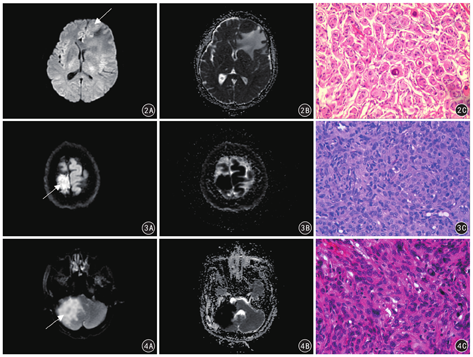

52例低级别组脑膜瘤中有38例DWI、ADC均呈等信号,14例DWI呈稍高信号、ADC呈稍低信号;16例高级别组脑膜瘤实质部分DWI均呈高信号、ADC均呈低信号,而囊变、出血坏死、钙化区均呈高信号。见图2,图3,图4。

MR DWI是目前体内测量水分子运动唯一的成像方法,其主要反应水分子活动的自由度,经ADC值可反应水分子的弥散系数。肿瘤实质ADC值的影响因素主要有:(1)肿瘤细胞密度,即肿瘤细胞密集和特殊的空间结构均可限制水分子扩散[7];(2)肿瘤细胞的异型性:异型性越高,细胞器越丰富,则降低细胞内水分子的扩散;(3)瘤内囊变、出血、坏死、钙化等均可改变水分子扩散运动;(4)T2穿透效应[8]。因此,ADC值越低,水分子受限程度越强。在乳腺癌、肝癌等肿瘤中已证实低级别肿瘤在DWI上的信号比高级别肿瘤低,ADC值较高级别肿瘤高[9,10,11]。本研究显示低级别脑膜瘤瘤体ADC和rADC值明显高于高级别脑膜瘤,原因可能是高级别脑膜瘤异型性高、排列密集、细胞密度高,细胞核大而深染,核仁显著,核浆比例增大,细胞器丰富,且有丝分裂活跃导致细胞外间隙缩小等限制水分子自由扩散,ADC值减低。而本研究中低、高级别脑膜瘤瘤周水肿部分ADC和rADC值差异无统计学意义,原因是脑膜瘤瘤周水肿与病理学类型有关,低级别脑膜瘤中的血管瘤型、分泌型、上皮型与高级别脑膜瘤中的非典型及间变型脑膜瘤的瘤周水肿较其他病理学类型脑膜瘤瘤周水肿明显[12,13]。本研究中未对低级别脑膜瘤的病理学类型进一步细分比较。此外,高级别脑膜瘤生长速度快,除了直接向周围组织浸润侵袭,引起邻近脑组织缺血缺氧,分泌致水肿分子如血管通透因子外,会对周围脑组织产生机械性压迫性水肿,是单纯的细胞外水分子的聚集,不是非细胞毒性水肿。

不同病理级别的脑膜瘤生物学行为和肿瘤质地存在差异,其MRI各序列信号表现有所不同,术前通过这些信号特征的差异可间接判断肿瘤的病理结构,区分脑膜瘤的低、高级别病理分型,甚至脑膜瘤的某些特殊病理亚型。但是,低、高级别脑膜瘤常规MRI影像学表现有一定的重叠,根据MRI常规序列区分脑膜瘤低、高级别存在一定困难。然而,低、高级别脑膜瘤瘤体实质的ADC值不同,且低级别脑膜瘤ADC值明显高于高级别脑膜瘤[14]。因此,通过测量脑膜瘤的ADC值可更好地预测肿瘤的性质及做鉴别诊断。本研究结果显示,高级别脑膜瘤的DWI表现为高信号、ADC图表现为低信号,其rADC值显著低于低级别脑膜瘤,低、高级别脑膜瘤ADC值差异有统计学意义。近年来研究发现,rADC较ADC值在颅脑肿瘤的鉴别诊断中有更高的敏感性和特异性[15]。我们进一步对低、高级别脑膜瘤瘤体实质rADC值进行ROC曲线分析,结果显示,诊断高级别脑膜瘤的最佳临界点为1.035×10-3 mm2/s,AUC为0.951,灵敏度为88.5%,特异度为87.5%。在鉴别低、高级别脑膜瘤上具有较高的灵敏度和特异度,可作为临床上鉴别低、高级别脑膜瘤重要的辅助诊断方法。